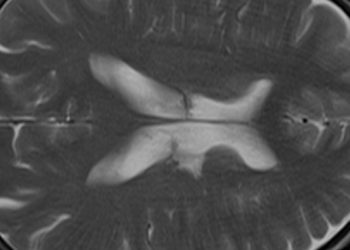

Study Rundown: An aggressive brain tumor with a poor prognosis, glioblastoma multiforme, is typically treated with a combination of surgical resection, chemotherapy, and external beam radiation. Despite multimodal therapy, these tumors frequently recur or progress and must be carefully followed with diagnostic imaging to guide decisions regarding their course of management. Contrast-enhanced MR imaging is currently the standard of care for tumor surveillance, but its performance is limited by post-treatment changes to the tumor bed. Specifically, increased MR contrast enhancement may be due either to true tumor progression or to benign, treatment-related inflammation, a phenomenon termed pseudoprogression. Features previously suggested to indicate true progression include a reduced apparent diffusion coefficient, increased cerebral blood volume, and a subependymal enhancement pattern, but none of these findings alone is sufficiently sensitive or specific to confidently register a diagnosis.

The current study sought to expand upon the available techniques used to identify true progression by utilizing calculated pharmacokinetic parameters of tissue permeability derived from contrast-enhanced MR-images. Among patients with treated glioblastoma, one pharmacokinetic value, the volume transfer coefficient (Ktrans), was found to be highly specific and moderately sensitive for true progression when increased. This finding was theorized to represent the increased neoplastic vascular burden or increased blood-brain permeability in the tumor bed among patients with progression of their disease. The study was limited by a small sample size and the lack of a comparison to standard imaging modalities used for the evaluation of tumor progression. Further studies incorporating traditional MR and diffusion-weighted imaging are warranted to examine the cumulative predictive effect.

In-Depth [prospective cohort]: Thirty-three patients with pathology-proven glioblastoma multiforme and new enhancing lesions within the tumor bed following surgical resection, external beam radiation, and temozolomide chemotherapy were examined using contrast-enhanced MRI with quantitative perfusion analysis. Using this technique, pharmacokinetic parameters such as Ktrans (volume transfer constant), ve (extravascular extracellular space) and vp (plasma blood volume per unit volume of tissue) were calculated for each patient. The presence or absence of true disease progression was determined by the Response Assessment in Neuro-Oncology (RANO) criteria, which specify a set of contrast-enhanced imaging findings that define true progression and pseudoprogression 12 weeks following completion of glioblastoma treatment. Quantitative MR imaging parameters were then compared to the RANO reference standard to determine the diagnostic performance of quantitative MR imaging in the diagnosis of true progression. Mean Ktrans was significantly elevated in the 17 patients exhibiting true progression versus the psuedoprogression group (P = 0.004), and mean ve was also significantly elevated in the true progression group (P = 0.034). Mean vp did not differ between the two groups (P > 0.05). Of these values, only an elevation of mean Ktrans beyond a threshold value of 0.347 min-1 was strongly predictive of tumor progression, with a sensitivity of 59% and a specificity of 94%.